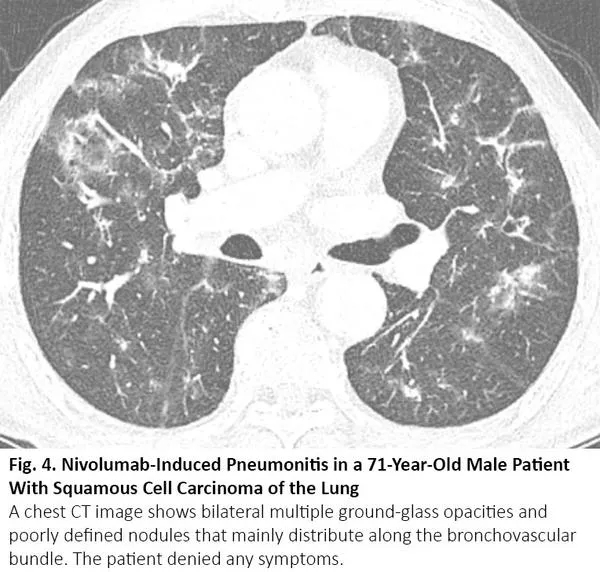

化疗、免疫治疗可引起药物性肺炎,导致CT呈现间质性肺部疾病的影像学表现。12最常见的类型是隐源性机化肺炎,其次是非特异性间质性肺炎、超敏性肺炎和急性间质性肺炎。13其中,隐源性机化肺炎、非特异性间质性肺炎的影像学表现可与COVID-19肺炎相似(图4),反之亦然。14

图4. 一位71岁肺鳞癌男性患者出现纳武利尤单抗治疗导致的肺炎